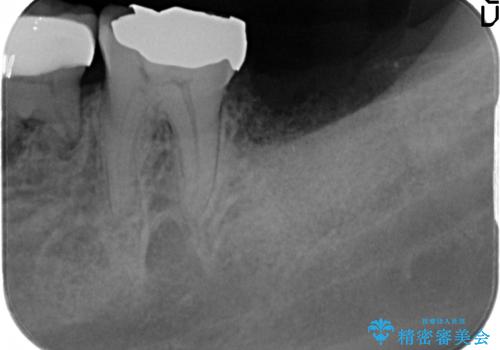

最後方臼歯周囲には大きな透過像が見られ、破折が強く疑われること抜歯が想定されることを理解していただき銀歯を除去したところ破折が認められたため抜歯を行いました。

良好なインプラントの植立を行うためには、十分な骨量があることが必須条件です。

術前、歯の破折により大きな骨の吸収が認められていたため骨量を十分に回復するために抜歯と同時に歯槽堤保存術を行い十分な骨量の回復をすることができました。